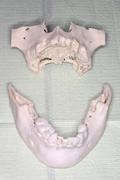

模型確認

必要に応じて患者さんの3次元顎体模型を作り、顎骨の形を事前に把握します。